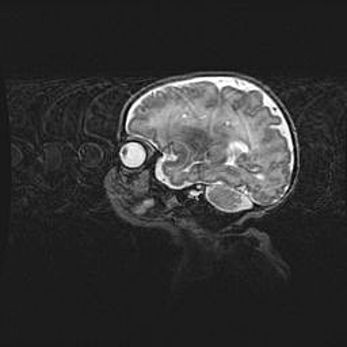

Церебральная ишемия II.

Возраст: 5 дней

Вес: 3400 г

Пол: женский

Окружность головы: 35 см

Срок гестации: 39 недель

Церебральная ишемия – это заболевание, характеризующееся недостаточностью (гипоксией) либо полным прекращением (аноксией) снабжения мозга кислородом по причине закупорки одного или нескольких сосудов. Это приводит к  что метаболическим расстройствам различной степени тяжести в тканях головного мозга, развитию коагуляционных некрозов и гибели нейронов.